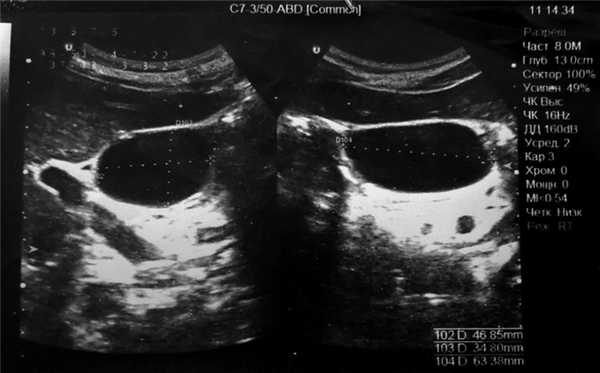

Клиническое наблюдение. Пациент П., 65 лет, обратился на консультацию в клинику факультетской хирургии им. И.И. Грекова СЗГМУ им. И.И. Мечникова 23.05.17 с диагнозом «киста холедоха» (общего желчного протока — ОЖП). Из анамнеза известно, что пациент считает себя больным около года, когда отметил появление чувства распирания и тяжести в верхних отделах живота, больше справа. Появление подобных жалоб ни с чем не связывает. Самостоятельно не лечился, за медицинской помощью не обращался. Ухудшение самочувствия отметил в конце апреля 2017 г., когда появились выраженные боли в правом подреберье, в связи с чем обратился в поликлинику. В амбулаторном порядке было выполнено УЗИ органов брюшной полости (рис. 1), при котором выявлено жидкостное образование в проекции ворот печени, которое было трактовано как киста ОЖП и рекомендована консультация хирурга-гепатолога.

Рис. 1. УЗ-скан образования брюшной полости.